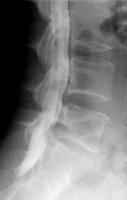

ミエログラフィー

背中に針を刺して、神経が通っている硬膜管内に造影剤を注入し、脊柱管の形状や障害を調べる検査です。

姿勢を変えたときの脊柱管の変化も見ることができるので、手術による治療計画を立てる際に役に立ちます。

ミエログラフィー後にCT検査を追加することで、より詳細に脊柱管の状態を見ることができます。